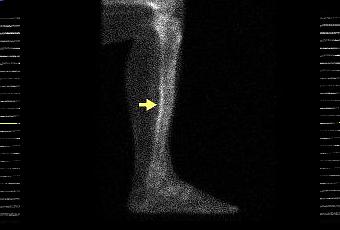

La périostite est l’irritation inflammatoire de la membrane externe de l’os. Elle est fréquente chez le coureur et elle se manifeste par une douleur ou une brûlure ressentie au niveau du tibia. Et je pense que j'ai cette pathologie.